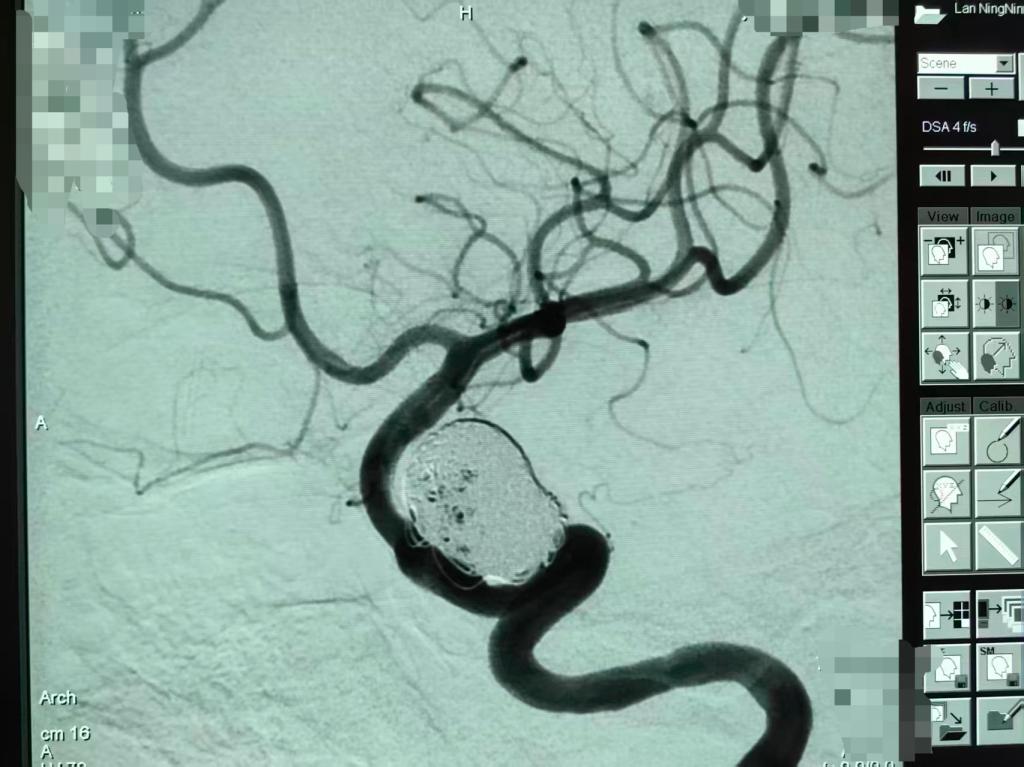

3、微创介入,精准治疗守护大脑健康

面对脑动脉瘤,现代医学的微创介入治疗已成为首选方案。西安凤城医院脑科病院神经外科常规开展的颅内动脉瘤栓塞术,仅需通过动脉穿刺,将微导管精准送达脑部动脉瘤内,用柔软的弹簧圈将其填满,从而彻底消除破裂风险。该技术无需开颅、创伤小、恢复快,医院凭借此技术已成功为众多患者拆除了颅内“炸弹”,术后效果良好,挽救了患者生命,提高了患者生活质量。